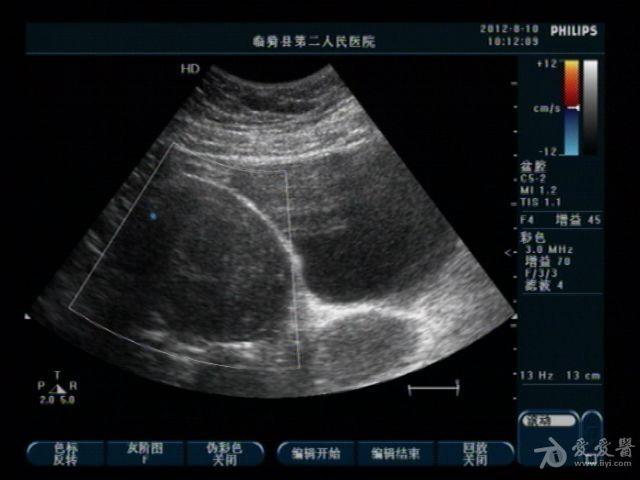

典型双子宫图像

前几天,我们科来了一位老病号,一年前剖腹产患者。当时手术证实“双子宫”今天超声图像可见一大一小两个子宫,右侧较大拟诊“子宫内膜异位症”。患者有经期腹痛史。

患者今年29岁,现生有一孩,就是剖宫产那个孩子。具体是那个子宫患者也不清楚,因在外地做的手术我们未能得到准确资料。患者近几个月来有明显的痛经史